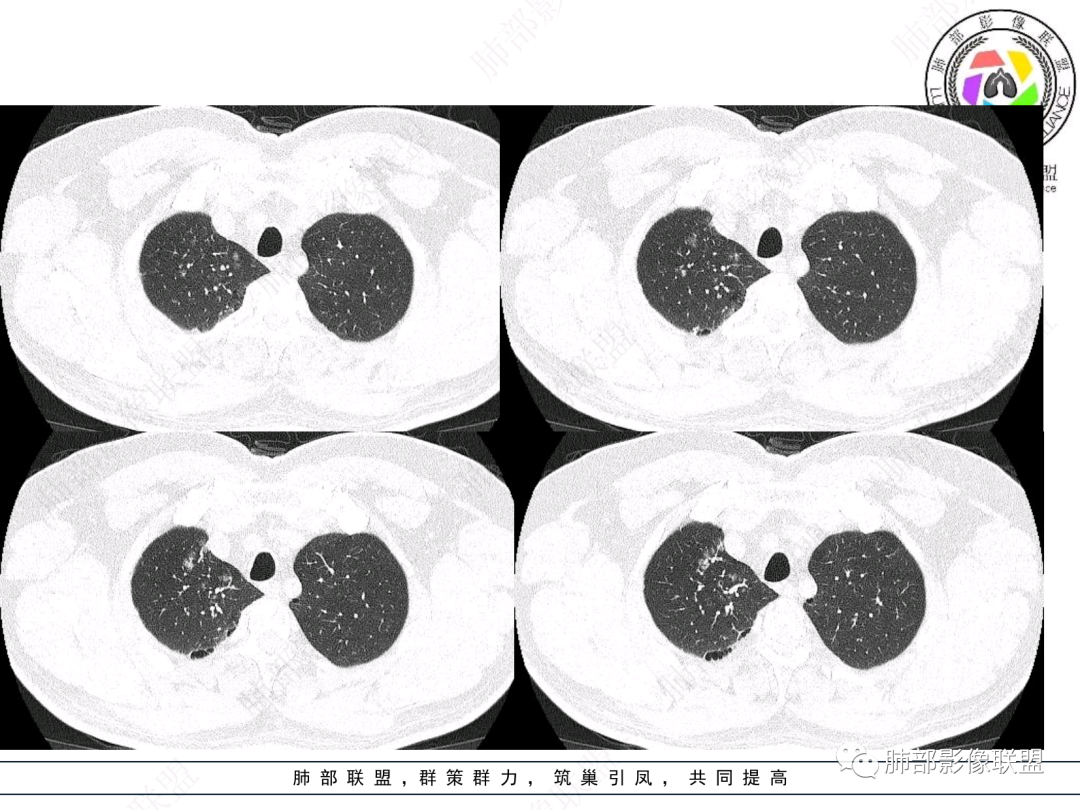

右肺上叶支气管截断,内见软组织密度结节,支气管管壁破坏,病变侵及管外,增强强化明显。右肺上叶沿气管血管束多发斑片影,考虑恶性性病变并阻塞性炎症,鳞癌,神经内分泌肿瘤。

右主支气管及肺门不规则软组织结节,点状钙化,不均匀强化,气管壁破坏,上叶支气管阻塞,分支粘液栓,血管束增粗,沿支气管分布多发结节,考虑鳞癌合并阻塞性炎症,鉴别结核。

右气管腔内结节,右肺门肿物,有钙化,右侧肺内多发气腔结节,散在,左肺部分支气管壁增厚,首先分析气管内结节,多考虑1鳞癌,形态规则,边缘光滑,宽基底,不太支持,远端阻塞性炎症不典型,2类癌,冰山一角和冰山分离了,不太支持3结核,多为支气管壁广泛增厚钙化,形成结节少,但是肺门肿块有钙化,可作为结核支持点,4黏痰,不像。其他不太懂了,肺内多发磨玻璃结节,并可见支气管手指状扩张,综合分析影像,考虑感染性病变,结核?有没有这样子的气管曲霉呢?向老师们学习。

男,52。间断咳嗽、咳痰2周,加重3天。胸部CT:右主、右上叶支气管多发软组织影,跳跃不连续,内可见小环状高密度,点状钙化,管壁破坏,上叶支气管堵塞,远端分支粘液栓,可见小支气管管壁增厚、管腔狭窄,沿支气管分布多发结节,无大片炎症不张。考虑:TB?NTM?鉴别Ca并阻塞性炎症。

患者中老年男性,咳嗽咳痰2周,无发热、咯血,伴胸闷、乏力及盗汗等,右上叶沿支气管血管束分布结节样变,管壁增厚;右肺门肿块,形态不规则、密度欠均匀,似有钙化,轻强化,主气道下端及右主支气管开口处见新生物,强化不支持类癌,镜下病变形态不大支持腺样囊性癌,考虑鳞癌可能性大,右肺上叶病变结核可能。

右肺上叶支气管开口见阻塞物影及强化,息肉样向腔内外浸润性生长,并有颗粒钙化,右肺上叶段支气管主干增粗及密度增高,见指套征,支气管血管旁见多发小斑点,小斑片影阻塞性炎性病灶〈小花小草表现〉,支气管镜示新生物血供丰富(结核完全排除),方向恶性,符合鳞癌特点,与小细胞Ca鉴定,临床专科支气管镜取材活检明确诊断。

腔内肿物,强化不均匀,强化程度为轻中度强化(CT值增加25HU),且强化特点为快进快出,右肺上叶支气管责任区域的阻塞性炎症加痰栓(气管镜也证实右上叶支气管内痰多)。这些均明确指向鳞癌。

一点不异常啊,分布在阻塞责任气管区域的支气管增粗伴腺泡结节(细支气管腔内及肺泡内阻塞性炎症伴痰栓),只不过还没有大片实变而已。@韩平     临沂市人民医院呼吸科

影像上分析的观察点:腔内、壁、腔外、远端,然后就是远端肺组织、淋巴结、肺血管、胸膜、其他肺部,这个人就是阻塞性炎症为主。